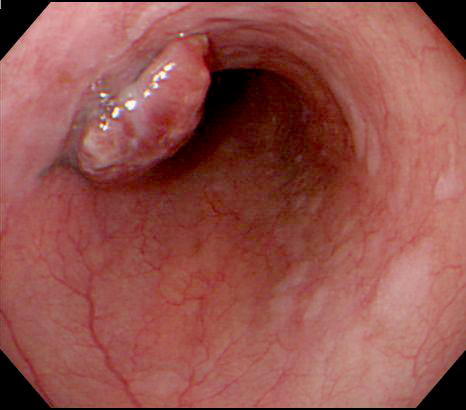

- Protruding tumor with pigmentation / black discoloration in the middle or lower esophagus

- Protruding / polypoid lesion with pigmentation / black discoloration (Oncol Lett 2019;18:1872, Histopathology 2021;78:240, Dis Esophagus 2019 Oct 30 [Epub ahead of print])